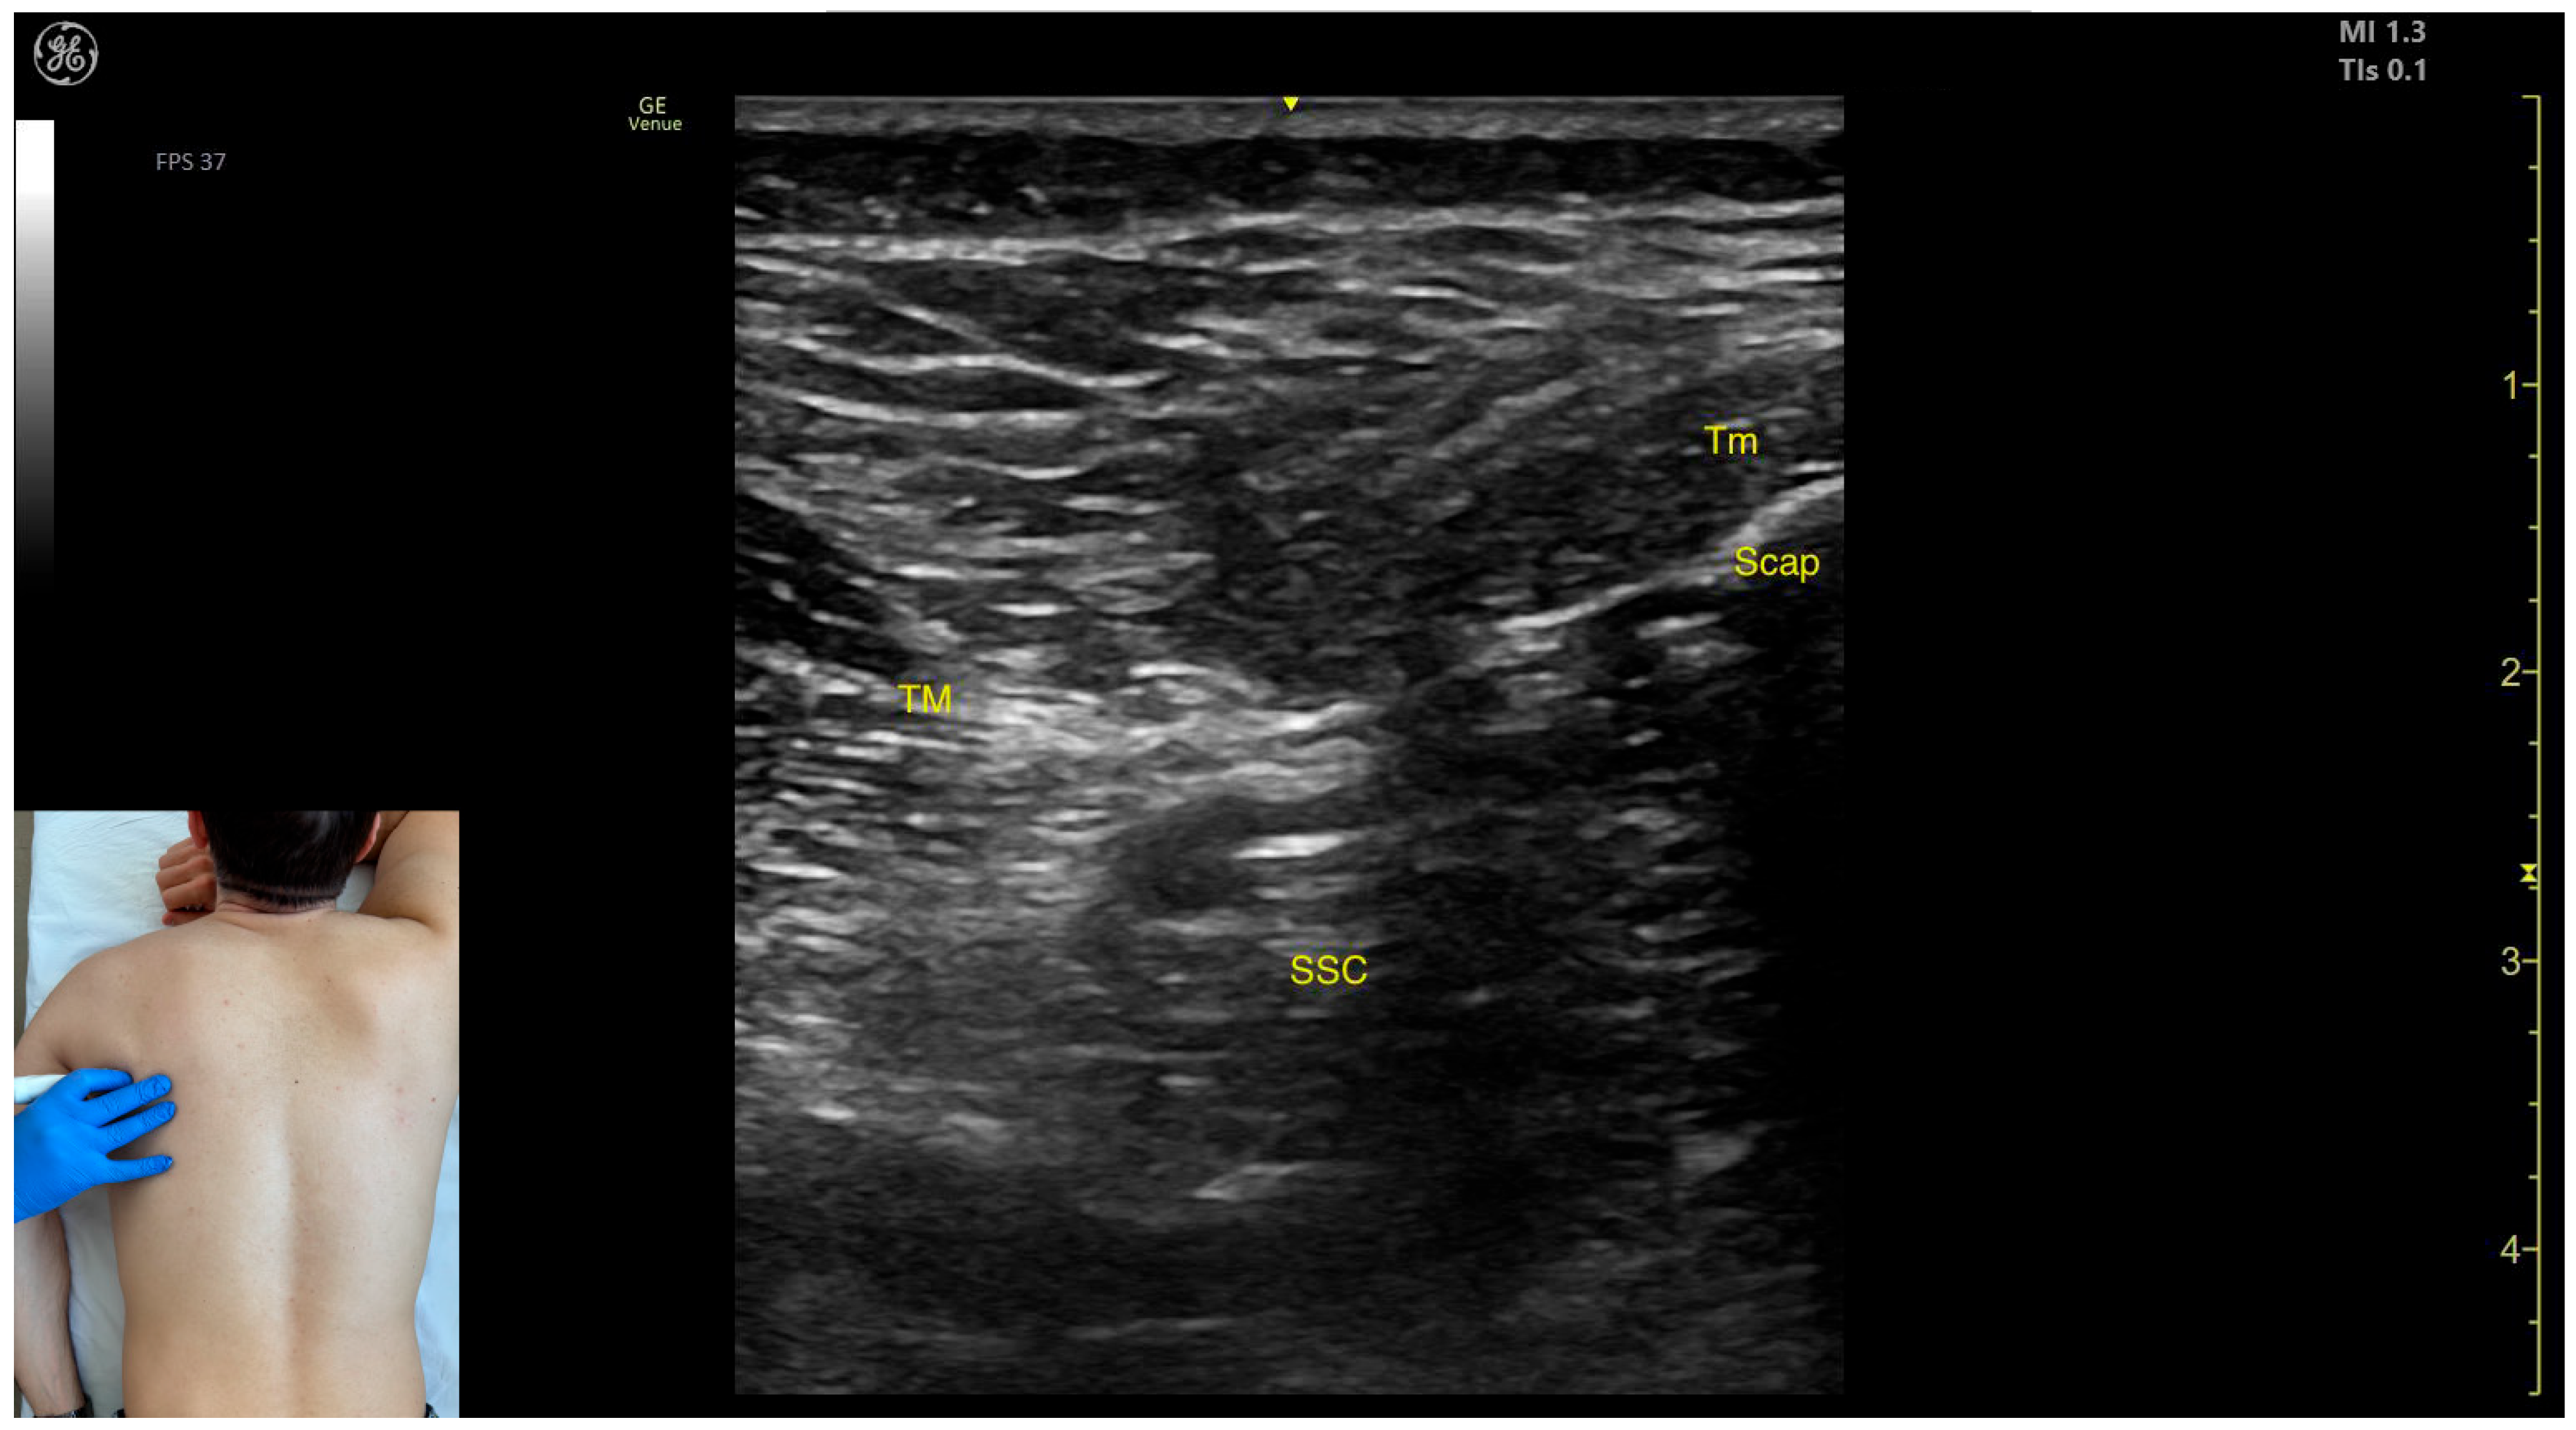

- Muscle morphology: The TM is a large muscle, visible from the depth of the rib cortex and intercostal muscles up to the subcutaneous plane.

- Muscle position: Medially and superficially, the teres minor (Tm) muscle is observed; medially and deeply, the subscapularis muscle and scapular cortex are visible; while laterally and deeply, the LD muscle is identified.

- External fascia: It has a pronounced fascia that separates it from adjacent muscle masses during BoNT-A injections.

- Dynamic evaluation: During dynamic evaluation, scanning proximally toward the axilla shows the transformation of the LD into a tendon, alongside which the TM forms the inferolateral portion of the posterior axillary wall [7]. The contraction of the TM is visible during adduction and internal rotation maneuvers of the humerus at the shoulder joint [12].